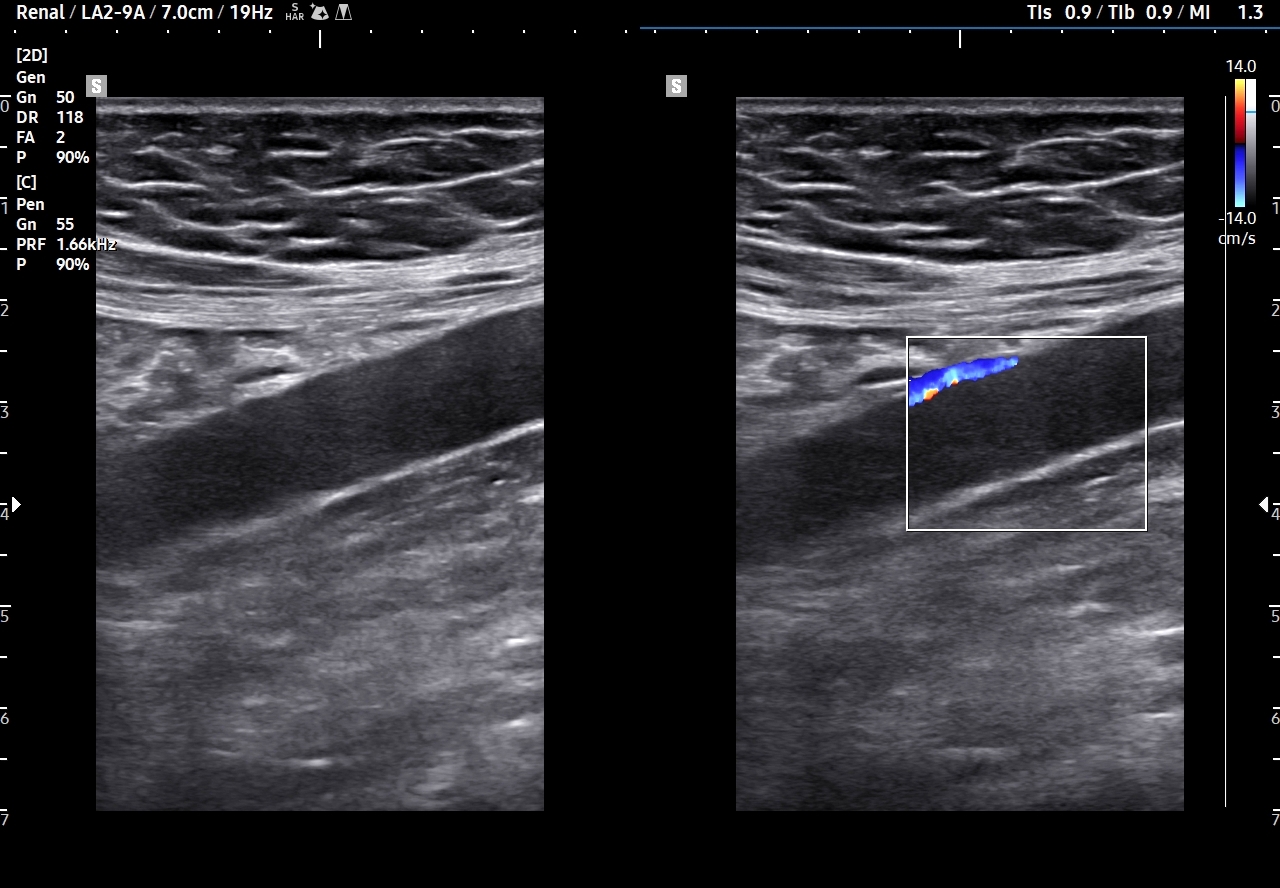

Endometrioza – metody diagnostyczne. Pierwszą linią diagnostyki endometriozy jest staranny wywiad oraz badania obrazowe w postaci USG transwaginalnego, USG przezbrzusznego oraz rezonansu magnetycznego MRI. Kombinowana czułość i specyficzność obu metod, tj. USG i MRI, sięga 90 %. Kolejnym etapem jest laparoskopia, która wykorzystywana jest zarówno jako procedura diagnostyczna, jak i lecznicza. W wyselekcjonowanych przypadkach endometriozy przydatne może być także badanie USG z kontrastem CEUS; np. do oceny zajęcia moczowodu.

W badaniu USG ogniska endometriozy zwykle przyjmują formę hypoechogennych guzków i nieregularnych mas; mogą być niejednorodne echogenicznie i zawierać drobne obszary torbielowate; w trybie color-Doppler i MVI wykazują skąpe unaczynienie.

Na skanach w niniejszym artykule zaprezentowany jest przypadek endometriozy głębokiej w miednicy mniejszej z intraluminalnym nacieczeniem dystalnego odcinka moczowodu, jego całkowitą niedrożnością i wtórnym wodonerczem. Choroba w tak zaawansowanym stadium wykryta została przypadkowo w rutynowym przezbrzusznym badaniu USG jamy brzusznej. W ramach diagnostyki różnicowej przeprowadzone zostały badanie CT, MRI oraz ureterocystoskopia z pobraniem materiału do badania histopatologicznego, na podstawie którego postawiono rozpoznanie endometriozy.